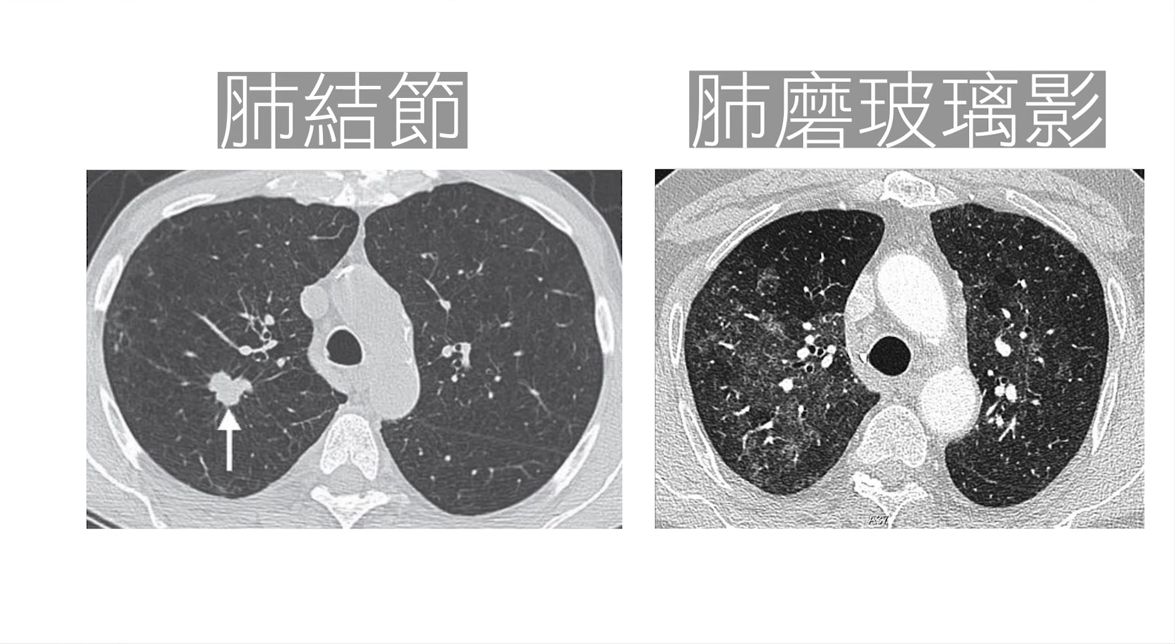

台灣胸腔暨重症醫師黃軒在其Facebook指出,2025年版新冠病毒「改玩『潛行』模式」,不少患者根本沒發燒,僅出現輕微腹瀉、疲倦、咳嗽等感冒般小症狀,等到發現時,肺部可能早已出現毛玻璃病變。因為病狀「輕微」,不少人照返工及聚會,致傳播風險更高。

🦠症狀輕微化|外表像感冒、腸胃炎,肺部卻可能默默出現「毛玻璃」(肺部出現磨砂玻璃影)